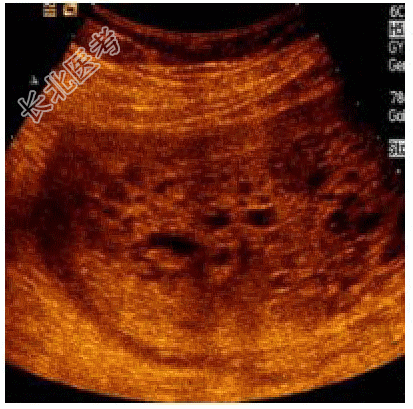

- 单项选择题孕妇,32岁, 孕2产0,停经12周5d。孕6周时尿HCG阳性。超声: 宫腔内未见胎儿回声,子宫矢状切面超声所见如下图。

最有助于诊断的检查是 A、血常规

B、血HCG

C、癌胚抗原(CEA)

D、超声造影

E、MRI